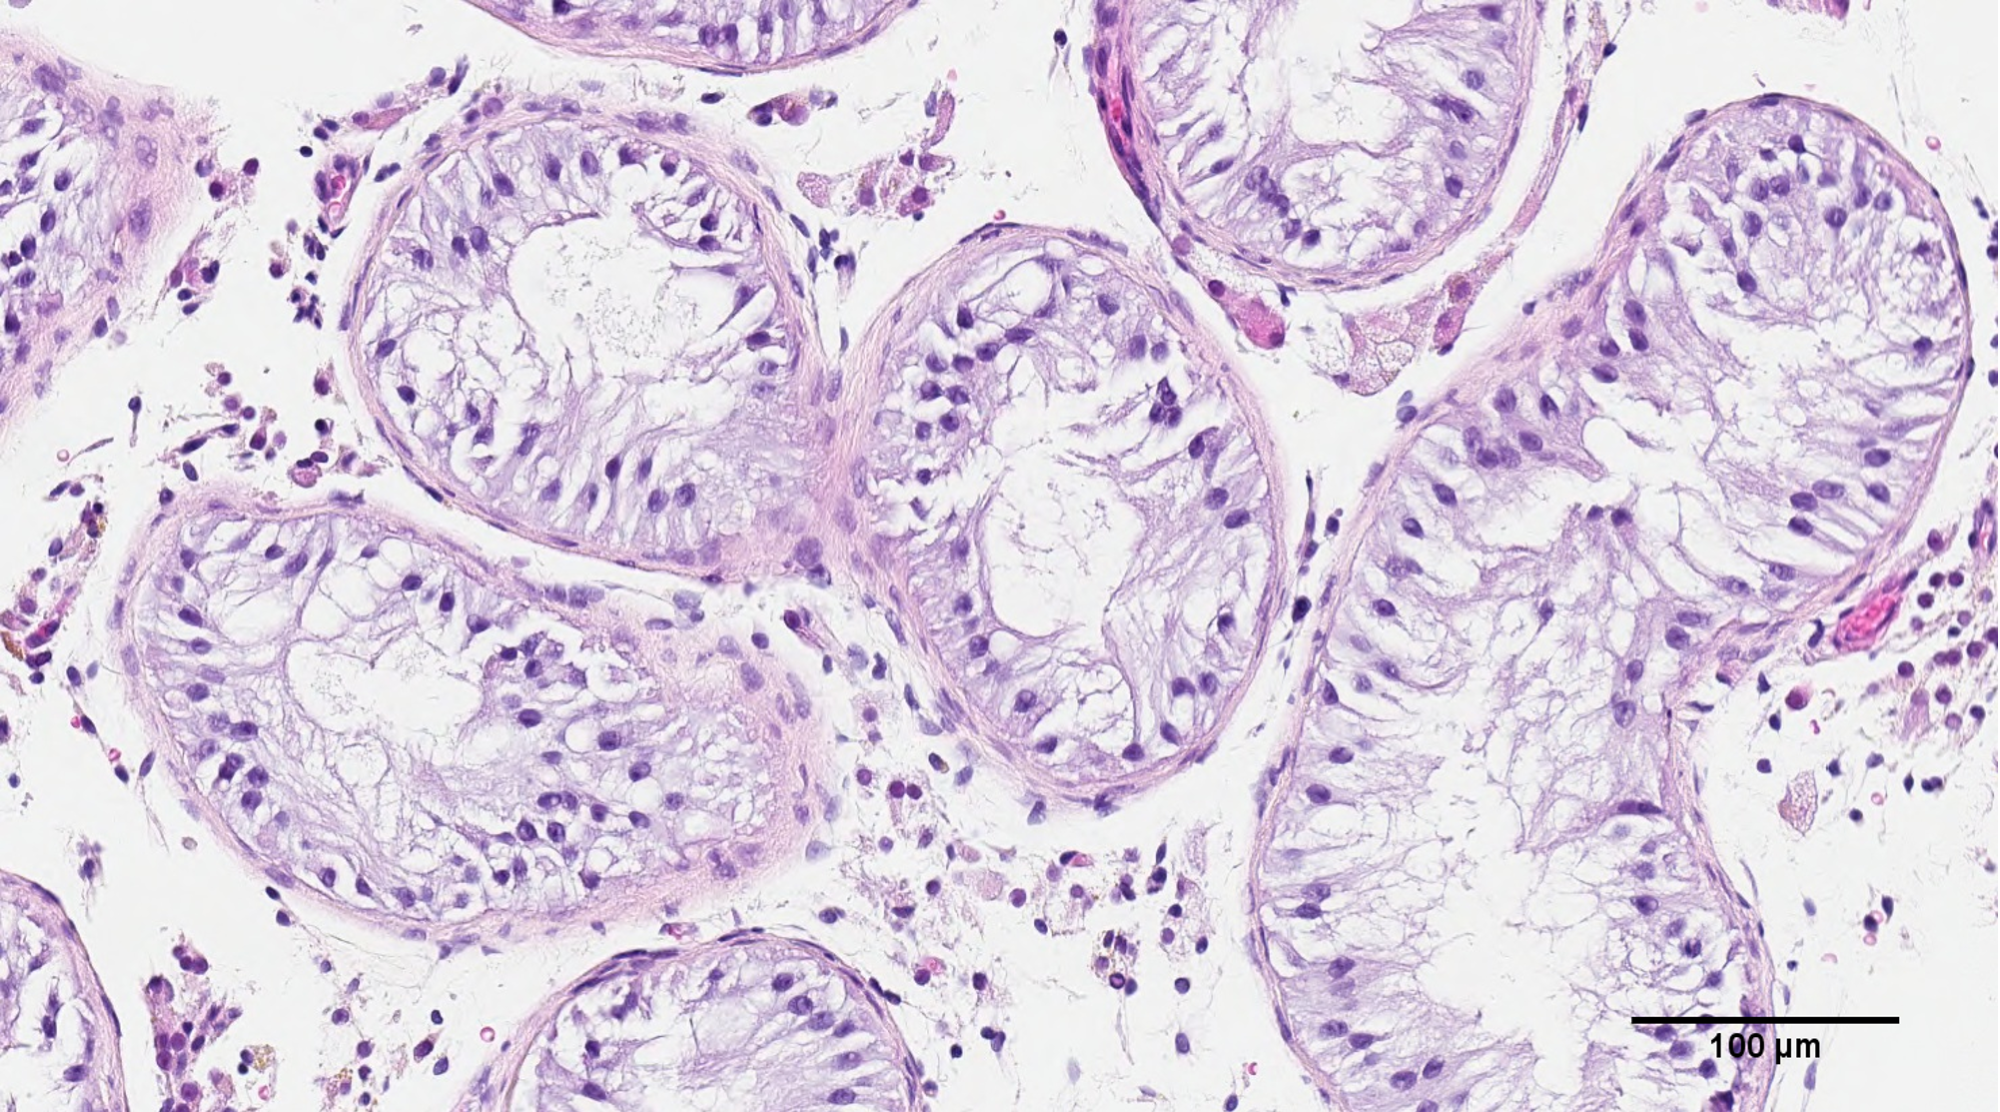

Our research is based on the understanding that normal sperm production is a highly complex and coordinated event among roughly 20 cell types within the testicle that require multi-directional cell communication through sending molecules between them or being in physical contact with each other. These interactions are specifically coordinated in the seminiferous tubule within the human testis.

We thought 3D printing cytoarchitecture as close to this physical structure as possible would serve as the most advantageous paradigm for us to build the rest of our research on. A lot of technical development in our protocols were necessary to produce the results in this paper, and we are currently working to continually refine our methodology and improve the technology.